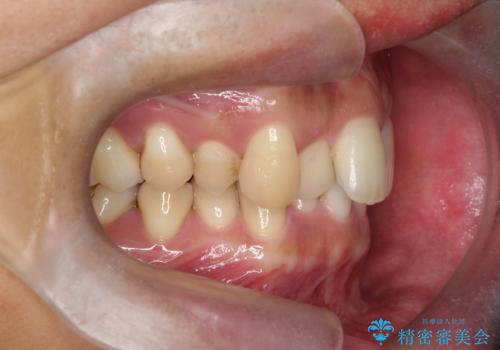

- 前歯のデコボコ(叢生)と、上下の歯の重なりが深い「ディープバイト(過蓋咬合)」を主訴にご来院されました。精密検査の結果、歯が並ぶスペースが不足しているため、上顎左右の小臼歯を抜歯することでスペースを確保し、全体の咬み合わせを改善する治療計画を立案しました。これにより、見た目の改善だけでなく、過度な咬み合わせによって生じる歯や顎への負担も軽減することを目指します。

今回の矯正治療では、まず歯が並ぶスペースを確保するため、上顎の小臼歯を抜歯しました。抜歯によってできたスペースを利用して前歯を奥へ移動させ、デコボコを解消。同時に、奥歯の咬み合わせを調整することで、深すぎた咬み合わせであるディープバイトも改善しました。治療の結果、長年気にされていた前歯のデコボコが解消され、理想的な歯並びに。さらに、正しい咬み合わせを獲得したことで、機能的にも安定した美しい口元になりました。